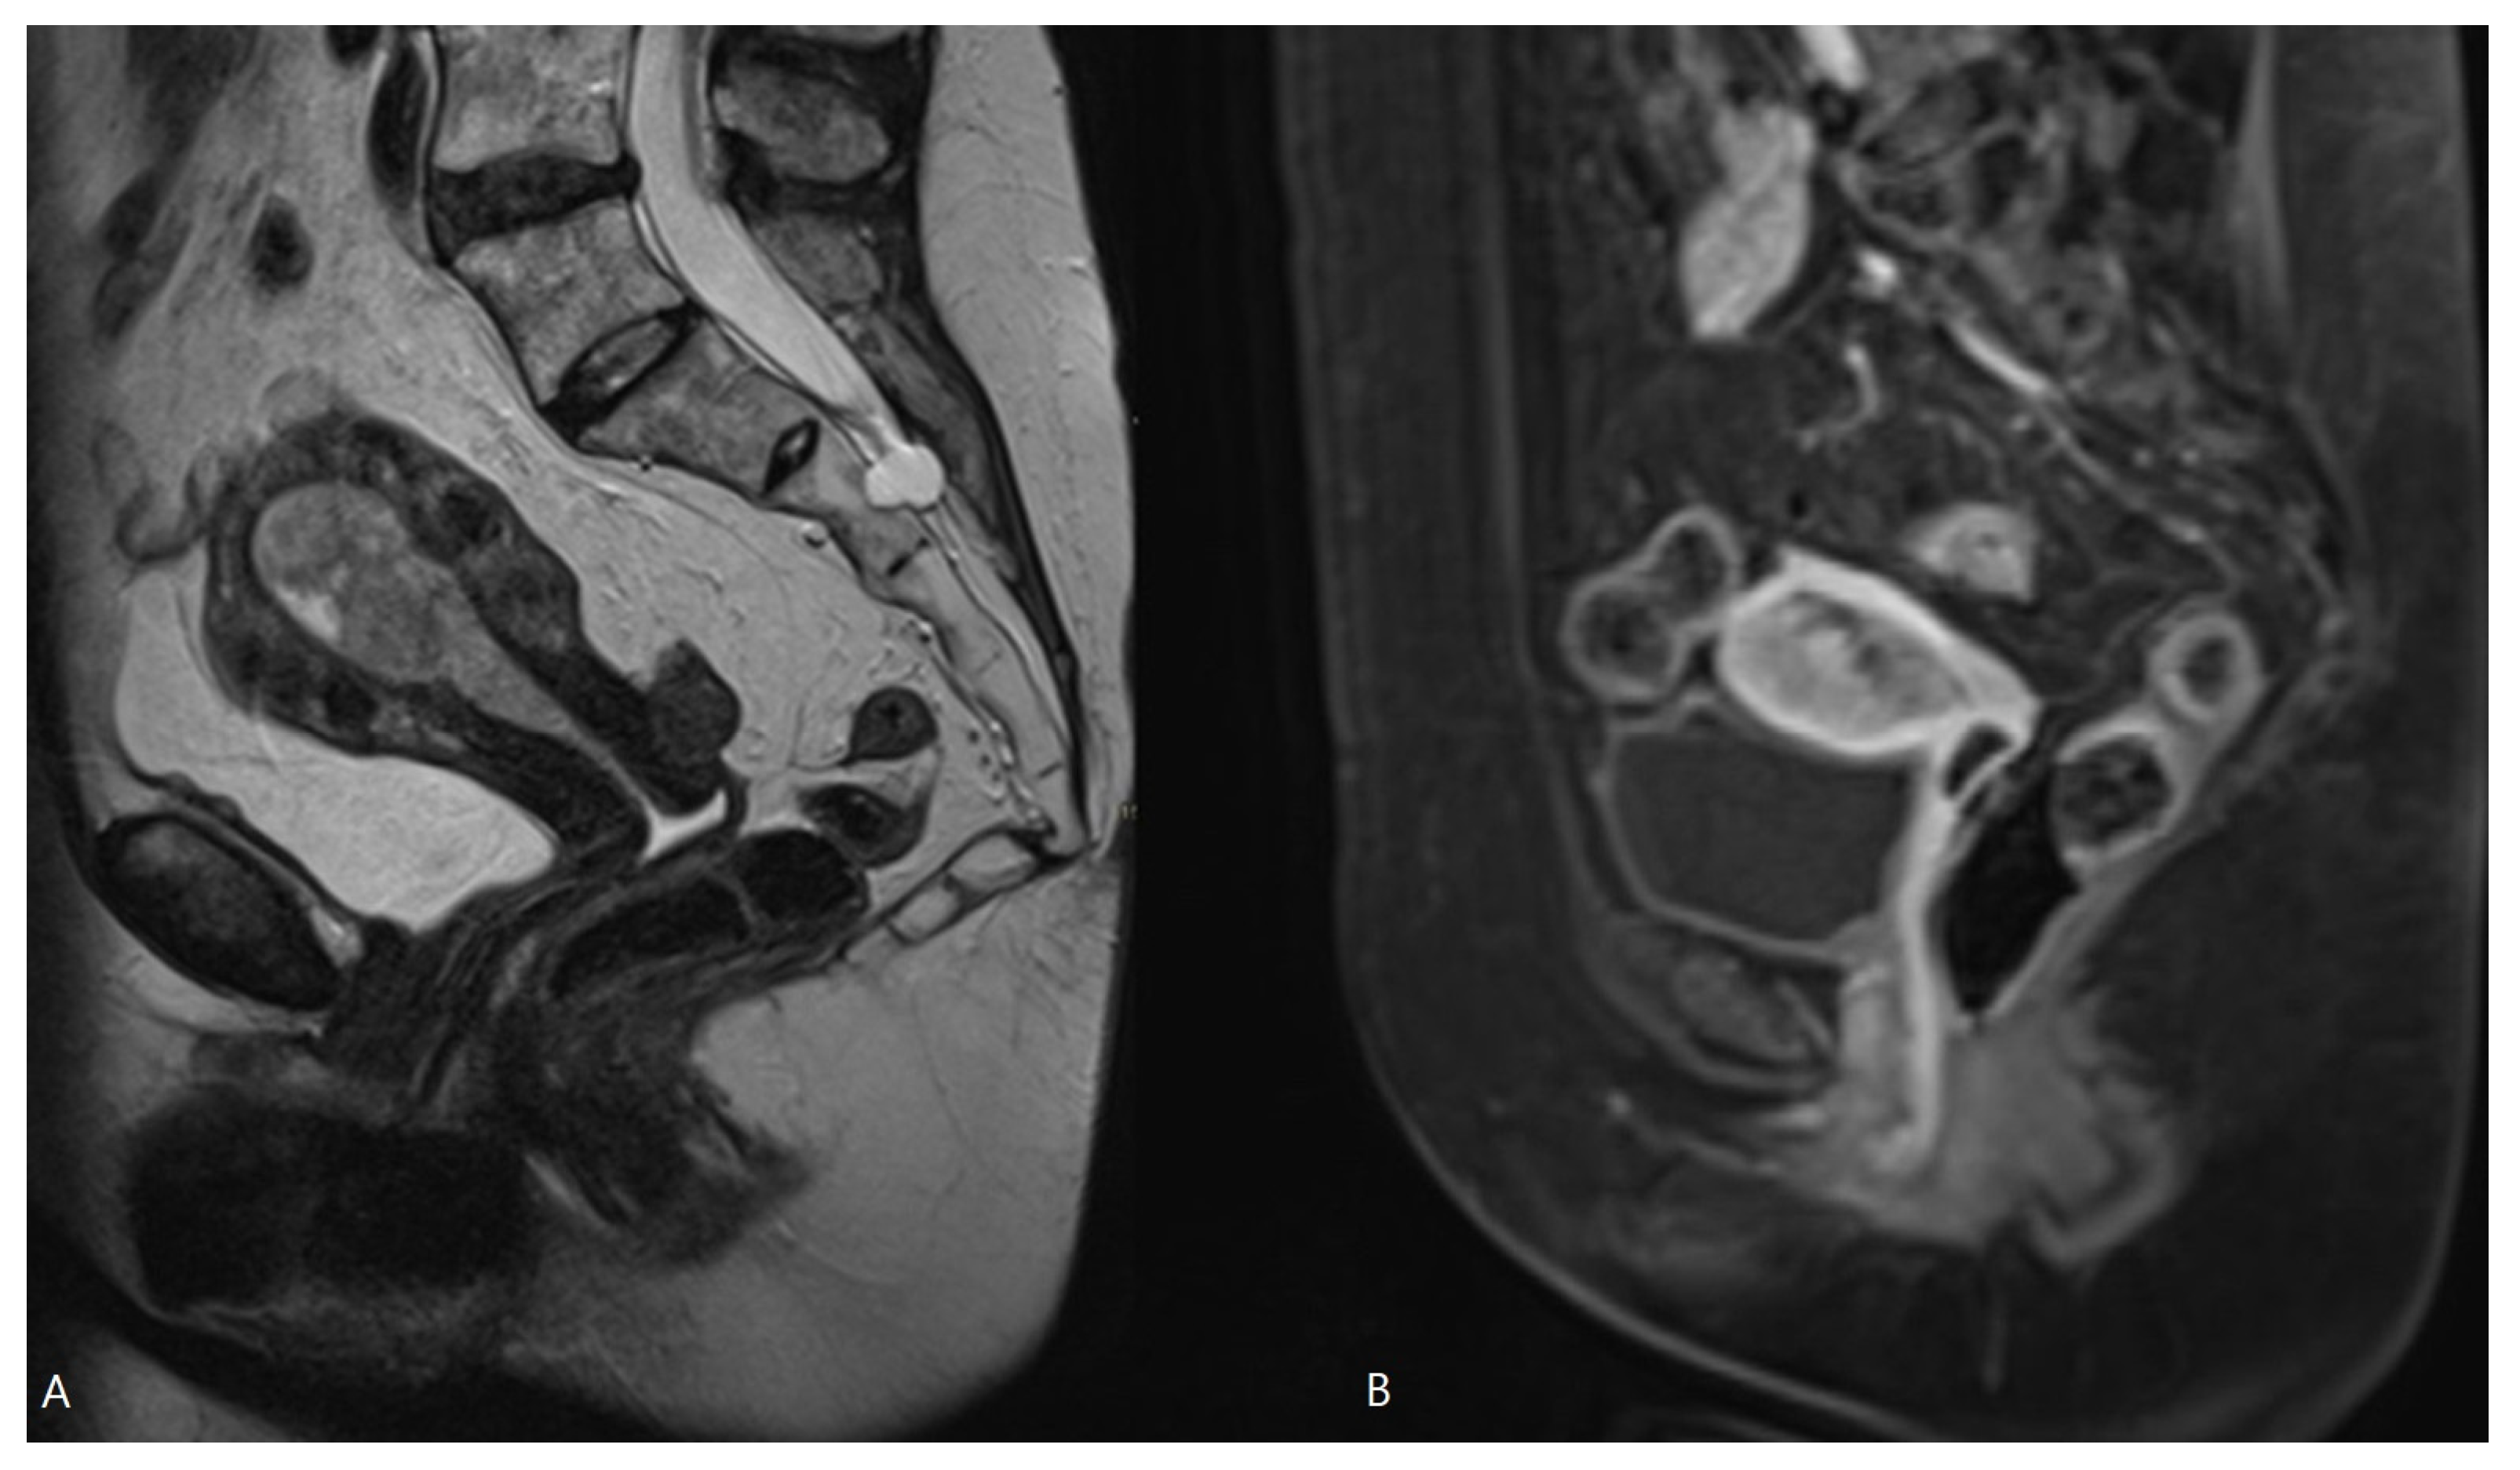

Hashimoto et al. [15] reported that preoperative MRI-based cancer stages and postoperative histopathological cancer stages were concordant in 70.0% of patients. The EC stage was underdiagnosed in MRI in 21.7% and overstaged in 8.2% of patients. This larger risk of understaging than overstaging with MRI was also observed in our study: the MRI-based T-stage was identical to the pathological T-stage in 57.1%, but the EC stage was underdiagnosed via MRI in 28.6% of patients and overstaged in 14.2% of patients. There are several causes reducing the accuracy of MRI in the local staging of EC. First, estimation of the depth of myometrial invasion is often difficult using MRI as the uterus grows atrophic in postmenopausal patients with an ill-defined junctional zone, hampering measurement of myometrial depth invasion. Moreover, in case of large or polypoid EC, or in the presence of concomitant leiomyomas or adenomyosis, myometrial compression by mass effect may further reduce the tumor-to-myometrium contrast, hampering image interpretation [8,11]. A polypoid EC bulging into the endocervical canal may be mistaken for a cervical stromal invasion, or an EC located intracavitary in the cornu may resemble tumor invasion in the outer half of the myometrium (Figure 3 and Figure 4).

Figure 4.

MRI of EC with bulging in the endocervical canal. Sagittal T2-WI (A) and sagittal T1-WI after Gadolinium administration (B). Histopathologically, this was pT1b disease, but in MRI there is risk of overstaging because tumor extension into the endocervical canal does not account for stage T2, which is preserved for cervical stromal invasion.